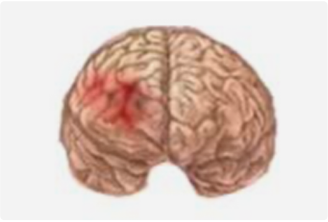

从事神经外科工作30年,擅长脑与脊髓血管类疾病、肿瘤、外伤等疾病的诊断与治疗,尤其擅长神经介入治疗各类脑血管疾病。累计完成介入栓塞颅内动脉瘤2000多例,颅内血管畸形数百例,夹闭颅内动脉瘤数百例,手术颅内与脊髓肿瘤数百例。在脑和脊髓血管病、肿瘤、外伤等方面有丰富的经验和较深造诣。

精通颅内动脉瘤介入栓塞和手术夹闭双技术,系统掌握脑动静脉畸形、颈内动脉海绵窦漏、硬脑膜动静脉漏等颅内血管疾病的诊疗和手术,精通颈动脉、椎动脉狭窄的血管内重建技术,以及颈动脉狭窄的内膜剥脱手术技术。在颅内肿瘤、椎管内肿瘤、颅脑损伤、高血压脑出血等疾病的诊治和手术,脑功能性疾病立体定向手术治疗等方面也积累了丰富的经验。

擅长脑血管病(出血与缺血)的神经介入与微创手术,能熟练开展脑外伤、重度颅脑损伤的救治工作。